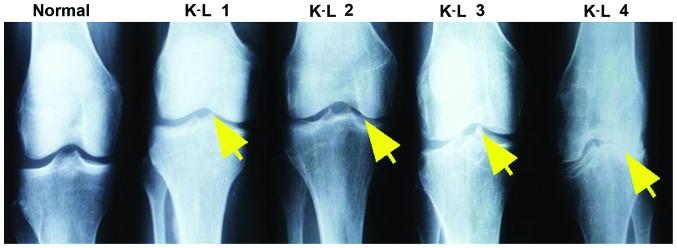

Macrophages, whether M1 or M2 subtype, have been found to be implicated in the pathogenesis of osteoarthritis (OA). However, no study regarding the status of M1 and M2 macrophages has been reported in knee OA. To investigate the status of M1 and M2 macrophages in knee OA, synovial fluid as well as peripheral blood were collected from 80 patients with knee OA and 80 healthy controls. Reverse transcription-quantitative PCR was used to quantitatively detect the expression of CD11c as a marker for M1 macrophages and CD206 as a marker for M2 macrophages from synovial fluids. As confirmation, flow cytometry was employed to count the number of monocytes from whole blood using the CD86 (M1) and CD163 (M2) markers on monocytes. The ratio of M1 to M2 macrophages was shown to be markedly higher in knee OA than that of control and that the ratio was significantly positively correlated with level of Kellgren-Lawrence grade in knee OA, that is, the higher the ratio the more severe the knee OA seems to be. Thus, our study presented direct evidence for the involvement of macrophages in the pathogenesis of knee OA.

巨噬细胞,无论是M1还是M2亚型,均被发现与骨关节炎(OA)的发病机制有关。然而,尚无关于膝骨关节炎中M1和M2巨噬细胞状态的研究报道。为了研究膝骨关节炎中M1和M2巨噬细胞的状态,我们从80例膝骨关节炎患者和80例健康对照者中采集了滑液和外周血。采用逆转录定量PCR法定量检测滑液中作为M1巨噬细胞标志物的CD11c和作为M2巨噬细胞标志物的CD206的表达。作为验证,采用流式细胞术,使用单核细胞上的CD86(M1)和CD163(M2)标志物对全血中的单核细胞进行计数。结果显示,膝骨关节炎患者中M1与M2巨噬细胞的比例明显高于对照组,且该比例与膝骨关节炎的Kellgren-Lawrence分级水平呈显著正相关,即比例越高,膝骨关节炎似乎越严重。因此,我们的研究为巨噬细胞参与膝骨关节炎的发病机制提供了直接证据。